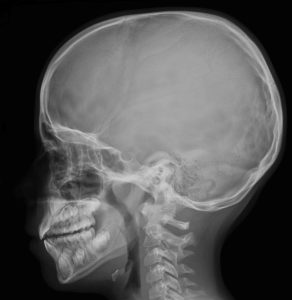

Kafatası röntgeni